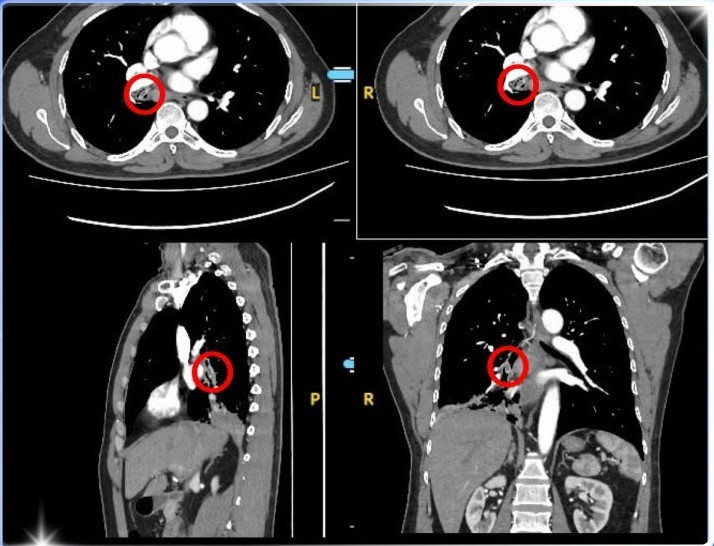

Tại phòng khám khoa Nội Tổng Quát, Bệnh viện Đa khoa Xuyên Á Long An, các bác sĩ tiến hành chụp CT scanner lồng ngực, kết quả cho thấy có dị vật hình bầu dục, kích thước khoảng 5,5 x 7,0 x 14,5 mm nằm trong phế quản gốc bên phải – nghi ngờ là một loại hạt trái cây mắc kẹt từ lâu.

Hình ảnh CT lồng ngực xác định nguyên nhân của việc ho dai dẳng - Ảnh BVCC